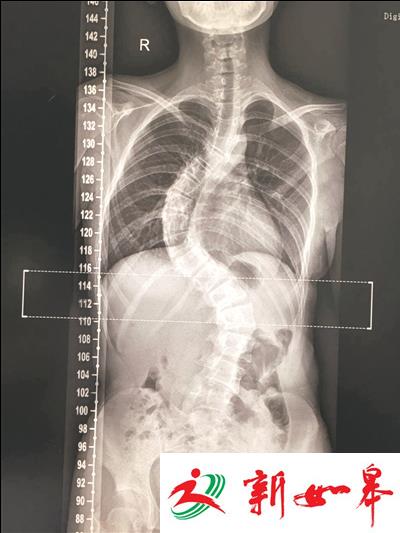

花季少女的背部呈现严重S型侧弯,已经影响肺部功能

“她的脊柱呈现S型侧弯,从胸2节段到腰4节段都存在严重畸形,已经开始影响孩子的肺部功能,可以说到了必须手术的时刻!”徐冠华说,严重的脊柱侧弯改变的不仅仅是她的外表,还有她本该天真烂漫的童真。医生的一番话,令这对老实巴交的安徽夫妇差点跪下来求医生救救孩子。